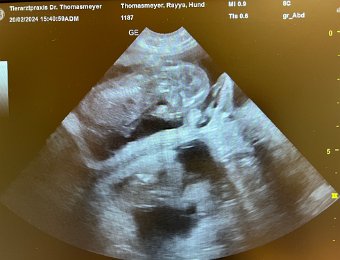

36. Tag

20-24.02.24